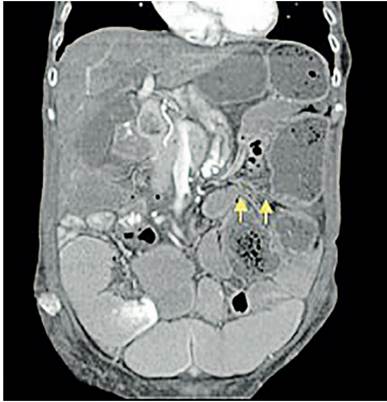

El hemograma no mostraba leucocitosis, la función renal era normal. La radiografía de abdomen simple (Figura 1) mostró una importante dilatación de asas, con niveles hidro aéreos escalonados, presencia de gas distal y materia fecal en recto. Se realizó una tomografía computarizada (TC) de abdomen con contraste (Figura 2) donde se documentó una zona de transición a nivel del colon sigmoide. Con diagnóstico de obstrucción intestinal colónica, fue llevada a laparotomía exploratoria encontrando hallazgos compatibles con vólvulo del sigmoide, por lo que se realizó sigmoidectomía y procedimiento de Hartmann. Durante la hospitalización presentó íleo postoperatorio prolongado, se descartó etiología mecánica y por antecedentes referidos, se consideró secundario a un trastorno de la motilidad gastrointestinal. Requirió nutrición parenteral total por 20 días y posteriormente fue dada de alta.

En la TC de abdomen (Figura 4) los hallazgos eran sugestivos de un vólvulo del ciego con obstrucción intestinal secundaria. Se realizó laparotomía exploratoria y se confirmó el diagnóstico (Figura 5), con hallazgos de ciego crítico dado por dilatación de hasta 15 cm de diámetro, dilatación del colon ascendente, transverso y de asas de intestino delgado, con cambios macroscópicos sugestivos de cambios crónicos por el compromiso gastrointestinal de su enfermedad de base.